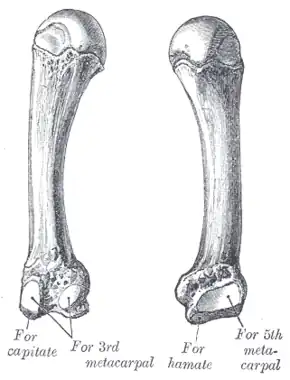

The fourth metacarpal. (Left.) | |

The fourth metacarpal bone (metacarpal bone of the ring finger) is shorter and smaller than the third.

The base is small and quadrilateral; its superior surface presents two facets, a large one medially for articulation with the hamate, and a small one laterally for the capitate.

On the radial side are two oval facets, for articulation with the third metacarpal; and on the ulnar side a single concave facet, for the fifth metacarpal.